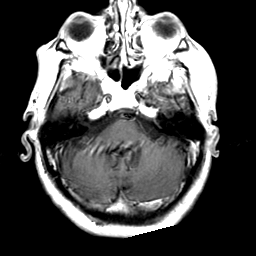

Meningioma, MR Study #2 -- Slice #4

[Home][Help][Clinical] Slice 4